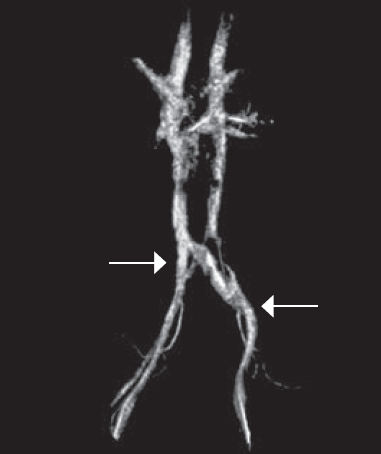

Центральный проксимальный артериовенозный конфликт илеокавального сегмента был выявлен у 4 (6,1 %), центральный дистальный — у 7 (10,6 %), левый проксимальный — у 52 (78,8 %), левый дистальный — у 31 (47 %), правый проксимальный — у 1 (1,5 %) и правый дистальный — у 1 пациента (1,5 %). При этом различные варианты сочетания артериовенозных конфликтов илеокавального сегмента были выявлены у 32 (48,5 % случаев) пациентов из 66 (рис. 2).

Рис. 2. Магнитно-резонансное исследование нижней полой вены и сосудов малого таза. Левый проксимальный и левый дистальный типы артериовенозных конфликтов илеокавального сегмента. Левой стрелкой указано место компрессии левой общей подвздошной вены правой общей подвздошной артерией. Правой стрелкой указано место компрессии левой наружной подвздошной вены левой наружной подвздошной артерией